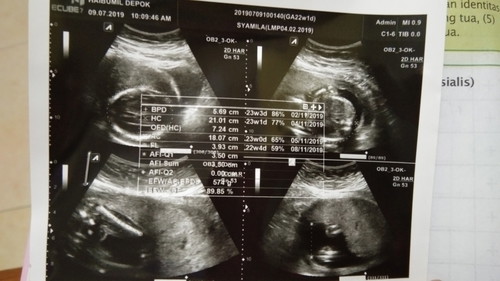

Tahun 2016 kami rasa tahun yg pas untuk kami melangsungkan pernikahan yg bisa dibilang dini ini. Usia saya tepat 19 tahun dan suami 22 tahun saat itu, di usia yg dikategorikan muda ini kami mantap untuk membina bahtera rumah tangga dan kami tdk ada rencana untuk menunda momongan bahkan diawal pernikahan kami sudah mulai mencari cara agar saya bisa hamil, namun ternyata mgkin belum waktunya. Tahun demi tahun kami lalui, karena panik belum juga diberi momongan dan stress dengan omongan orang, saya memutuskan untuk konsultasi ke dokter kandungan sebagai ikhtiar kami untuk segera diberi momongan. Sesampainya di dokter kandungan betapa sedihnya kami saat mendengar ternyata saya menderita PCOS (Polystic Ovary Syndrom) dan sempat diberitahu oleh sang dokter bhwa saya akan sulit untuk memiliki keturunan dan dokter menyarankan program hamil dengan bantuan medis, karena kami sangat menginginkan anak kami menyetujui program2 yg disarankan dokter. Setahun berlalu dari rujukan dokter tapi garis dua tak kunjung tiba, akhirnya kami mencari alternatif lain yg lebih mudah pikir kami. Tapi ternyata memang mungkin belum waktunya jadi tetap nihil. Saya mulai banyak baca artikel tentang PCOS ini akhirnya saya memulai konsisten hdup dengan pola hidup sehat terutama tdk makan karbohidrat slama bbrapa bulan dan rutin olahraga alhasil berat badan saya turun dan siklus menstruasi kembali normal di 30 hari. Tahun 2018 kabar duka menyelimuti keluarga kami karena ayah saya meninggal tepat di bulan kelahiran dan pernikahan saya, berat badan saya kembali turun begitu juga dengan kondisi kesehatan saya. Tapi qodarullah tepat sebulan setelah kepergian ayah saya kabar gembira menghampiri kami, penantian 2 tahun akhirnya tiba. Strip 2 akhirnya muncul juga di testpack masyaa Allah. Tapi sepertinya kebahagiaan itu ujian buat kami, di akhir 2018 saya keguguran karena ternyata kehamilan saya kosong atau BO, kami pasrah kali ini sudah lillahita'ala kami serahkan semuanya kepada Allah subhanahuwata'ala. Berkat kepasrahan kami kepada sang Rahman dan Rahim alhamdulillah awal tahun 2019 Allah titipkan kembali janin yg sehat dan sempurna hingga saat ini sudah menginjak 23w5d dengan jenis kelamin laki2. Semoga saya dan suami bisa menjadi orgtua yg amanah karena penantian ini. Aamiin Allahuma Aamiin. #CeritaHamilTAP ❤